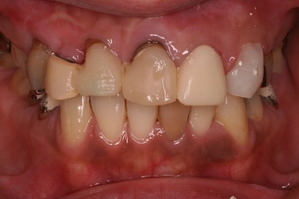

おそらく、数年前はきれいな差し歯が入っていたと推測されます。

正面からみると歯茎の黒ずみがきになります。原因は2つあり、ひとつは金属の土台から溶出される銀イオンです。もう1つは、歯を削るときにでる切削片が歯肉の中に入り込んでしまうのです。どちらも時間の経過とともに目立ってきますが、最近の審美治療ではこのようなことが生じません。